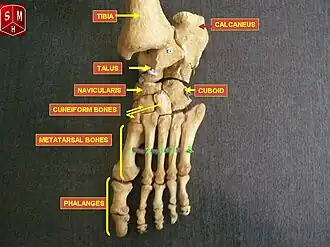

Bones of the human foot, with navicularis labeled at upper left in image. | |

The navicular bone in humans is one of the tarsal bones, found in the foot. Its name derives from the human bone's resemblance to a small boat, caused by the strongly concave proximal articular surface. The term navicular bone or hand navicular bone was formerly used for the scaphoid bone,[1] one of the carpal bones of the wrist.

The navicular bone in humans is located on the medial side of the foot, and articulates proximally with the talus, distally with the three cuneiform bones, and laterally with the cuboid.

The navicular bone is a keystone of the foot: it is part of the coxa pedis and articulates with the talus, first, second and third cuneiform, cuboid and calcaneus. It plays an important role in the biomechanics of the foot, helping in inversion, eversion, and motion; it is a structural link between midfoot and forefoot and it is part of the longitudinal and transverse arch of the foot.